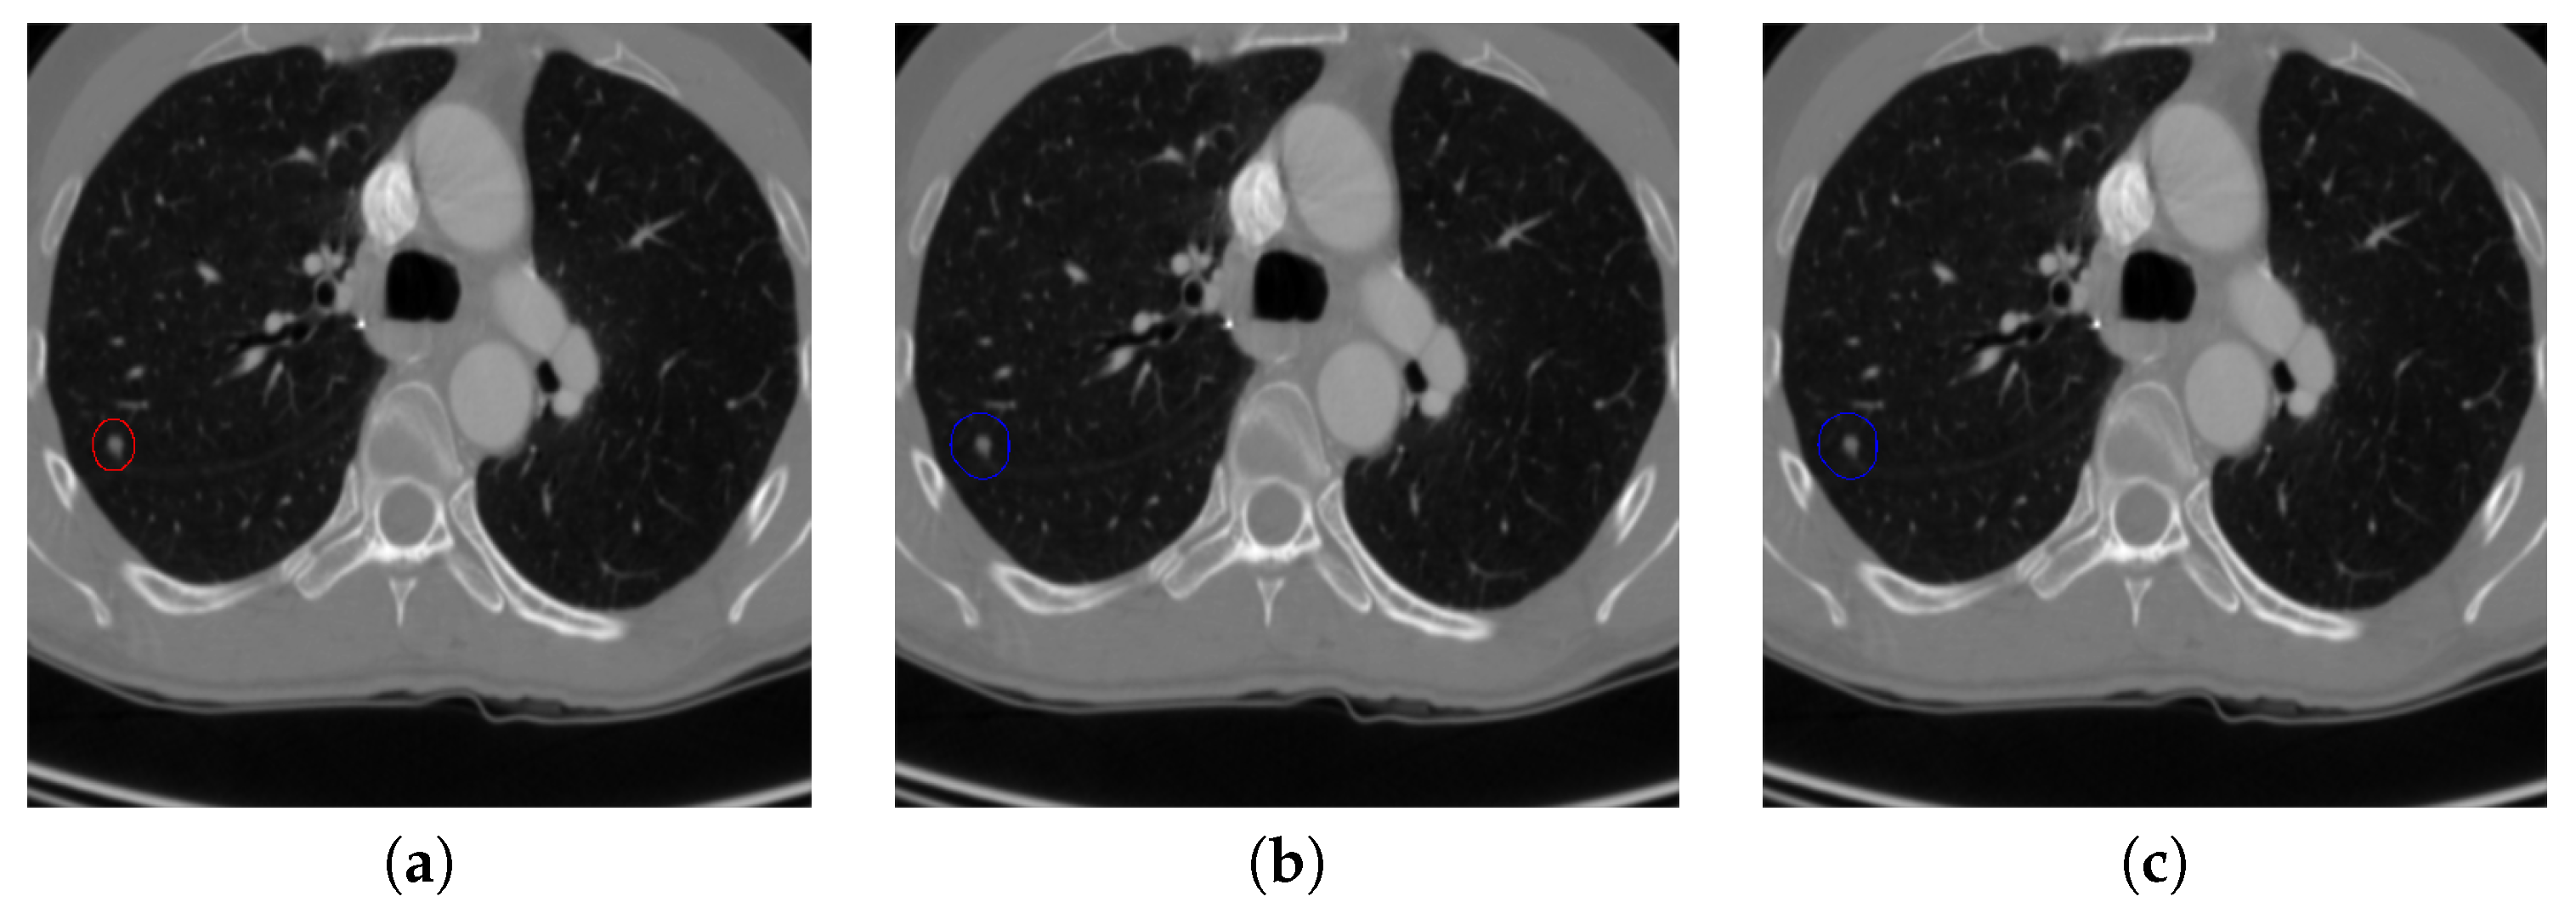

Figure 20. The result of detecting pulmonary nodules by different methods on another example image in TianChi dataset. Red circle represents the ground truth region of nodules, blue circles represent the correct estimation of pulmonary nodules, green circles represent the over-detected nodules, while yellow circles denote the nodules being omitted. (ai) are: ground truth nodule in the given chest CT image, nodule detected by 3D-FCN, MR-CNN, 3D-UNET, PRN-HSN, DCNN, CLAHE-SVM, MASK-RCNN and our proposed method.

Figure 17 and Figure 18 illustrates the performance of pulmonary nodule detection by different methods on two example images in the LUNA16 dataset. In addition, Figure 19 and Figure 20 illustrates the performance of pulmonary nodule detection by different methods on two examples images in the TianChi dataset. As marked by green circles in Figure 18b,c and Figure 19c, the 3D-FCN and MR-CNN directly detected the nodule candidates from the original CT image without pre-processing, resulting in the incorrect determination of non-nodule tissue outside lung as nodule since the outside-lung organs are not filtered out from the nodule candidates. The 3D-UNET and PRN-HSN add the lung parenchyma region segmentation stage before detecting the nodule candidates inside-lung, so they provide better performance than 3D-FCN and MR-CNN in decreasing the over-estimation rate. However, they still suffer from unsatisfactory results for the following reasons: (1) the lung parenchyma segmentation is generated by simple thresholding with morphological operations so the near-edge regions are lost, shown as the one marked by yellow circle in Figure 20d,e; (2) the convolution kernel used in nodule candidate detection of 3D-UNET is with a small receptive field to learn global features from the image, so it is likely to confuse some small tissues as true nodules with small sizes, shown as the one marked by green circle in Figure 18d and Figure 20d; and (3) the proposed hierarchical saliency network (HSN) in PRN-HSN for nodule candidate classification omits the information with different resolutions, resulting in that the small-size nodule within the weakened, low-resolution region cannot be correctly recognized, as shown by the yellow circle in Figure 18e. The DCNN method simply applies the Faster RCNN method to provide good performance with low computational cost, but it may omit the nodules on the parenchymal edge shown as yellow circles in Figure 20f. CLAHE-SVM method adds a contrast-enhancement pre-processing before the nodule detection, leads to better performance on detecting nodules in the low-contrast region. However, it is easily to over-enhance the small-size tissues and over-estimate them as nodules, as shown by the green circles in Figure 19g andFigure 20g. The detection is also implemented over the whole image, so the nodule on the parenchyma edge may be under-estimated show by the yellow circle in Figure 20g. The Mask-RCNN method provides better effects than the above methods because of the good performance of Mask-RCNN in object detection. However, the performance is not stable for the small-size tissues and the irregular-shape nodule, shown by the green circles in Figure 17h and Figure 19h, and the yellow circle in Figure 19h. The proposed method takes the advantage of a series of U-Net-like networks to perform the nodule detection following a “coarse-to-fine” order of inside-lung region detection, nodule candidate detection and nodule determination. The U-Net network is modified by embedding inception structure, replacing the convolution and pooling by dilated convolution, and adapting multi-scale pooling and multi-resolution convolution connection, for different requirements of the three stages, respectively. Moreover, it makes use of the MSE loss, VGG-19-based perceptual loss as the complement of dice loss to optimize the whole framework. Therefore, as shown in Figure 17i, Figure 18i, Figure 19i and Figure 20i, the proposed framework provides superior performance on pulmonary nodule detection with low over-estimation of non-nodule tissues at the same time.